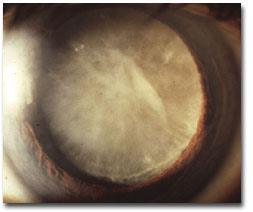

iii. Lens opacification: including types of cataract, relationship of opacity to symptoms, contribution to visual loss in co-morbidities; systemic associations; cataract surgery and its complications.

iv. Pseudoexfoliation of the lens capsule: including its recognition and significance.